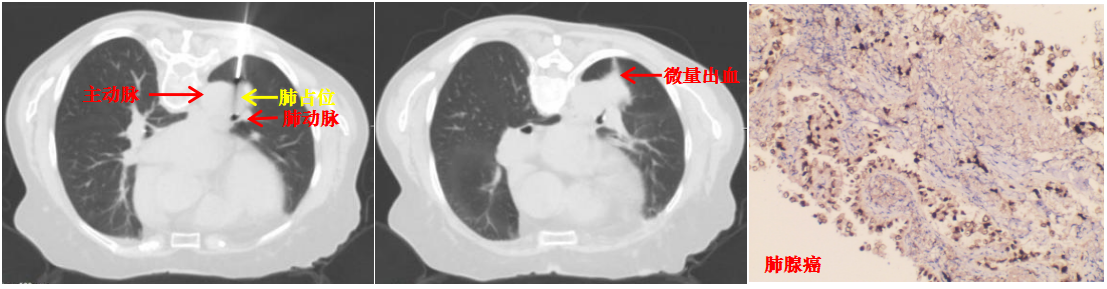

本病例患者肺结节穿刺中(左图)、穿刺后(中图)和病理诊断(右图)

取得患者及家属同意后,陆霓虹主任带领介入团队医生杨嫄、贺晓洁,护士杨红艳、王丽,在CT引导下实施穿刺活检。影像监控下,针尖精准抵达病灶核心,实时测量显示针尖距离主动脉仅4mm,团队迅速完成切割取材,仅出现极少量创面出血,对症处理后患者安返病房,无出血、气胸等并发症。

术后病理确诊为肺腺癌,为患者后续治疗提供了决定性依据。此次技术突破,是科室在高危肺结节诊疗领域的又一跨越。未来,亚洲色吧 附二院呼吸与危重症医学科介入团队将持续精进技术、优化诊疗流程,为更多高危肺结节患者提供精准、安全的微创诊疗服务。